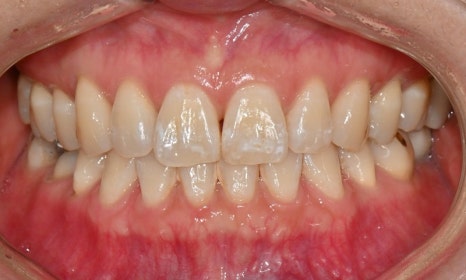

미백 후 브라켓 주변 white spot

교정이 끝난 후 브라켓 주변이나 치아와 잇몸 사이 경계 부위에서 탈회로 인한 백색 반점(white spot)이 생기는 경후도 흔히 관찰됩니다. White spot은 치아의 겉껍질(법랑질, 에나멜) 구조의 변화에 의한 것으로, 미백으로 개선되지는 않으며 오히려 미백 치료 후에 더욱 두드러지게 보이게 됩니다. 따라서 미백을 하기 전에 환자분들께 이 부분에 대한 설명을 충분히 해드린 후 진행하게 됩니다.

이러한 white spot은 미백을 하고 난 후 1~2주 정도 지나면 치아 내부의 수분이 안정화되고 미세한 재광화가 일어나면서 색대비가 자연스럽게 완화되지만, 만약 white spot에 대한 적극적인 개선을 원할 경우 미백을 한 후 최소 2주 정도 시간이 지난 후 ICON 치료(레진침투치료)를 고려할 수 있습니다.